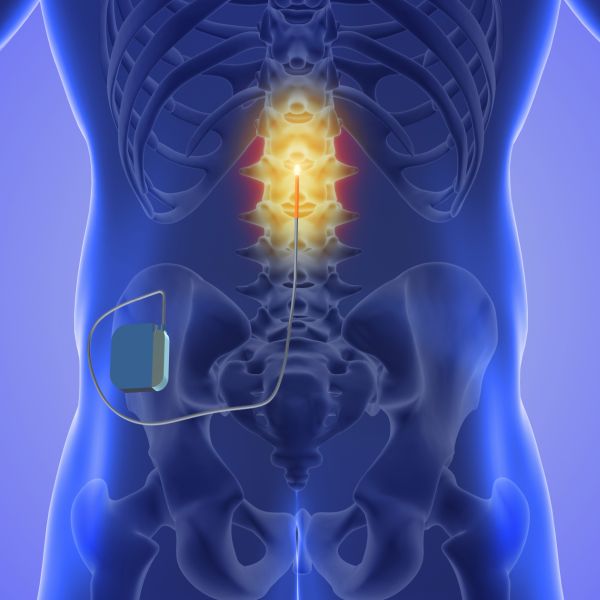

Περιγραφή της μεθόδου

Για την εφαρμογή της διέγερσης νωτιαίου μυελού, ένα ή παραπάνω ηλεκτρόδια εμφυτεύονται με τοπική αναισθησία και ακτινοσκοπική καθοδήγηση στον επισκληρίδιο χώρο, στο οπίσθιο κέρας του νωτιαίου μυελού, και σε επίπεδο το οποίο αντιστοιχεί στο δερμοτόμιο όπου παρουσιάζεται ο πόνος. Τα ηλεκτρόδια συνδέονται μέσω υποδόριας διαδρομής με εμφυτεύσιμη γεννήτρια. Η ηλεκτρική ενέργεια που παράγεται από τη γεννήτρια εφαρμόζεται μέσω των ηλεκτροδίων στις κατάλληλες περιοχές του νωτιαίου μυελού.

Για την αξιολόγηση του θεραπευτικού αποτελέσματος της νευροδιέγερσης, πραγματοποιείται δοκιμαστική νευροδιέγερση λίγων ημερών. Εφόσον ο ίδιος ο ασθενής διαπιστώσει σημαντική ανακούφιση (>50%) και δώσει τη συγκατάθεσή, ακολουθεί η εμφύτευση του μόνιμου συστήματος. Σε περίπτωση που δεν επιτευχθεί ικανοποιητικό αποτέλεσμα, τότε απλά αποσύρεται το ή τα ηλεκτρόδια που είχαν τοποθετηθεί. Πρόκειται για μια πλήρως αντιστρέψιμη θεραπεία, κάθε σύστημα νευροδιέγερσης μπορεί ανά πάσα στιγμή να αφαιρεθεί σε περίπτωση ανάγκης χωρίς καμία παρενέργεια.

Ο προγραμματισμός του συστήματος γίνεται τηλεμετρικά με ειδικό προγραμματιστή, υπάρχει δυνατότητα αλλαγής και εφαρμογής διαφόρων συνδυασμών ώστε ο ασθενής να λαμβάνει το βέλτιστο θεραπευτικό αποτέλεσμα. Ο ίδιος ο ασθενής φέρει και αυτός προγραμματιστή τσέπης τον οποίο μπορεί να διακόπτει, να ενεργοποιεί και να αυξομειώνει την ένταση του διεγέρτη.